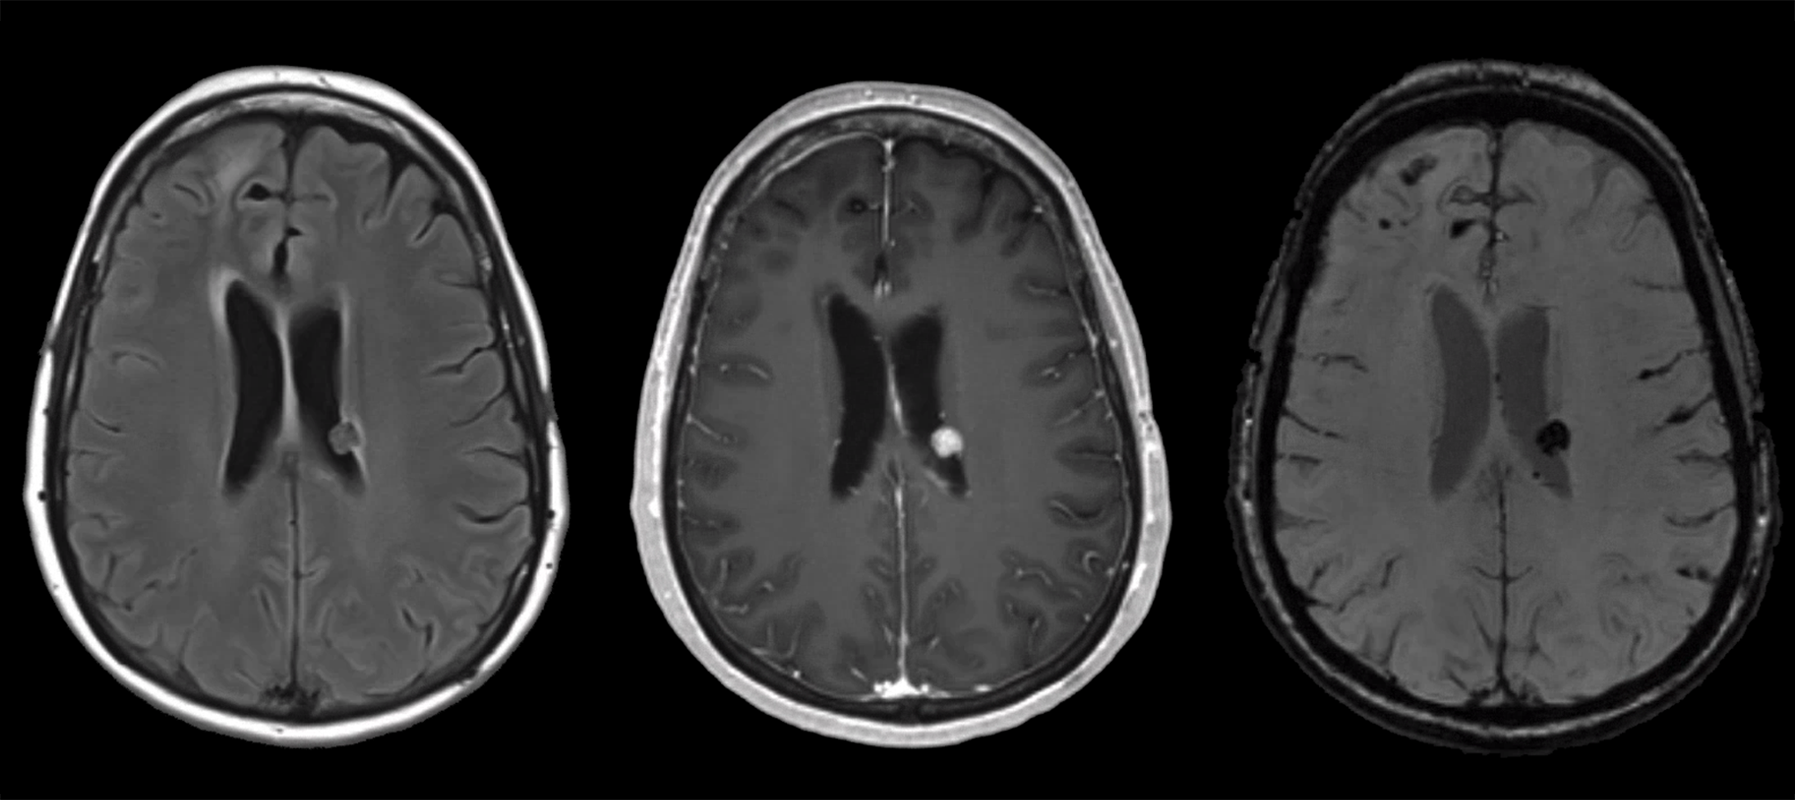

She woke up this morning and her legs "gave out" when she walked to the bathroom. Her hands shook bilaterally. She tried to speak, but her husband said she was "garbled" and nonsensical. Symptoms stopped once she got back in bed. She was able to speak short sentences. This episode lasted about two minutes in total. Her husband drove her to the ED. There, initial vitals are notable for BP 179/73, HR 63, SpO2 99% on room air, T 36.4C. Initial labs are notable for WBC 13, Hb 12, Plt 250, Na 133, Cr 0.7, uNa 179, uOsm 941, sOsm 274. A non-contrast HCT was obtained and is shown below. Her neurologic exam remains slightly abnormal: she is somnolent but does briskly awaken to verbal stimuli. She has no clear focal weakness or hypoesthesia. You were then consulted.

HCT part 1 HCT part 2 HCT part 3

Looking at her non-contrast HCT now, there's nothing new in terms of acute hemorrhage or large-territory infarction, nor overt vasogenic edema. Now we should compare this to the prior scan. It's not shown well in these example slices shown here, but her ventricular caliber was very subtly larger as compared to the MRI, most noticeable with the slightly larger temporal horns and third ventricle.

Our leading diagnosis at this point is epileptic seizure. You hear that our neurology colleagues are already recommending repeat imaging and EEG, and they'll also start levetiracetam. Repeating an MRI is reasonable because she's already demonstrated cancer progression in spite of her therapy, and she's now having new symptoms. Her HCT doesn't clearly reveal anything that requires acute neurosurgical intervention. She has expected post-operative changes related to her frontal lobe metastasis resection. Her ventricles are questionably larger, but because of the temporal relationship with the steroid taper, you don't think this is responsible for her presenting symptoms. Her ependymal nodule certainly isn't the major contributor of her problems.